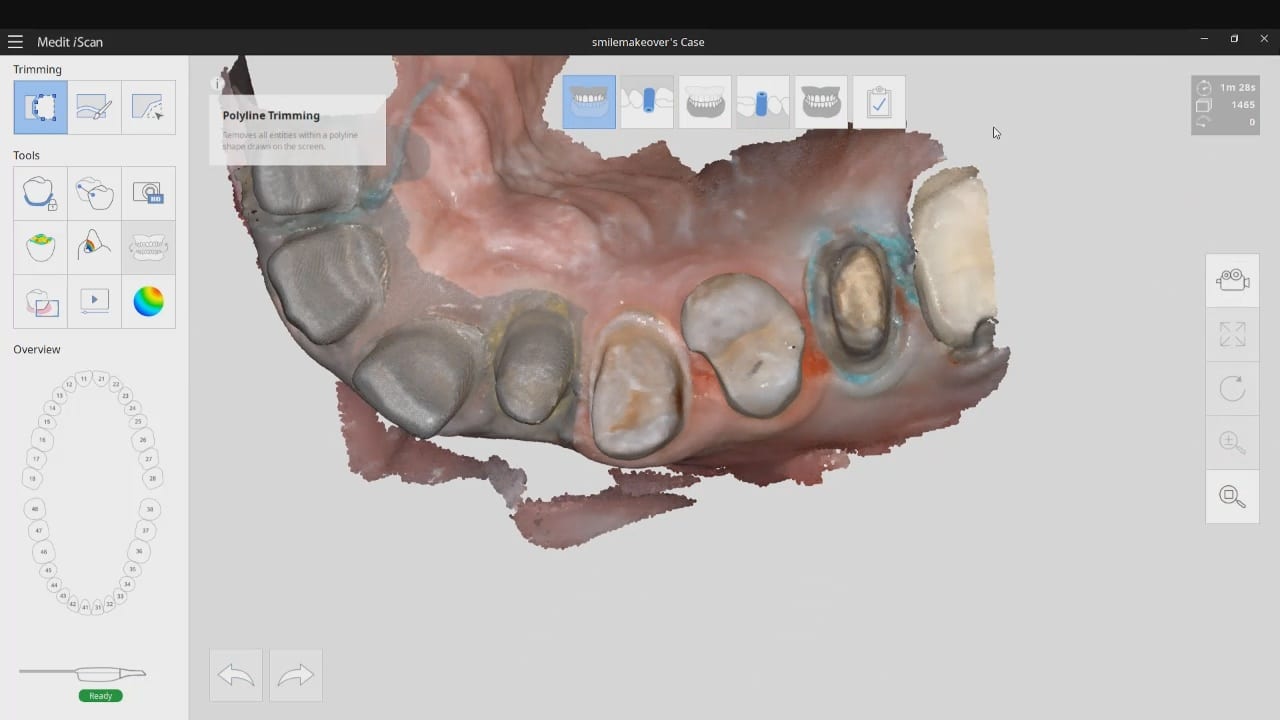

segmental imaging to building a master model

upper and lower models related to each other for design